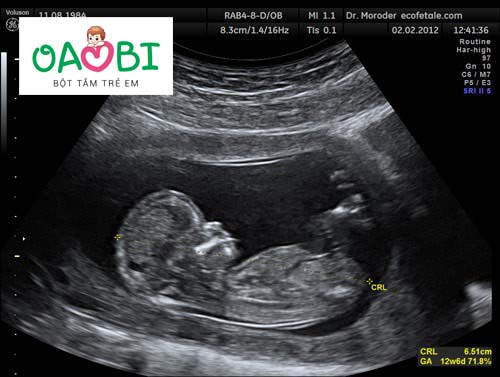

Khoảng sáng sau gáy bao nhiêu là bình thường?

Đo khoảng sáng sau gáy là một trong những chỉ số vô cùng quan trọng khi đi khám thai mà bất cứ mẹ nào cũng cần phải thực hiện. Bởi thông qua kết quả này sẽ giúp chẩn đoán xem bé có mắc hội chứng Down hay không từ đó giúp phát hiện các dị tật nhiễm sắc thể khác.